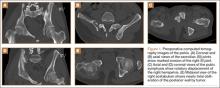

Figure 1 shows the patient’s computed tomography (CT) scan. Figures 1A and 1B reveal fragmentation of the posterior ilia and sacrum along both SI joints. Dislocation of the pubic symphysis is shown in Figures 1C and 1D, and discontinuous involvement of the ischium and posterior wall of the acetabulum is visible in Figure 1E.